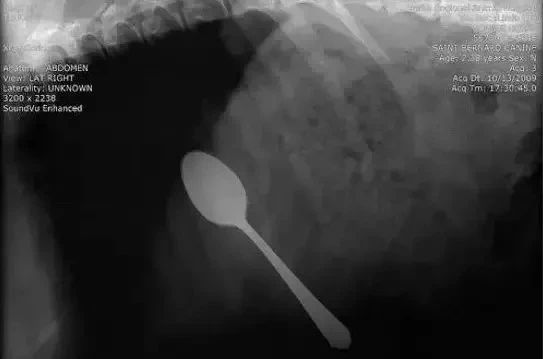

吞了一整只勺子是什么鬼!经过咽喉不用拐弯吗?